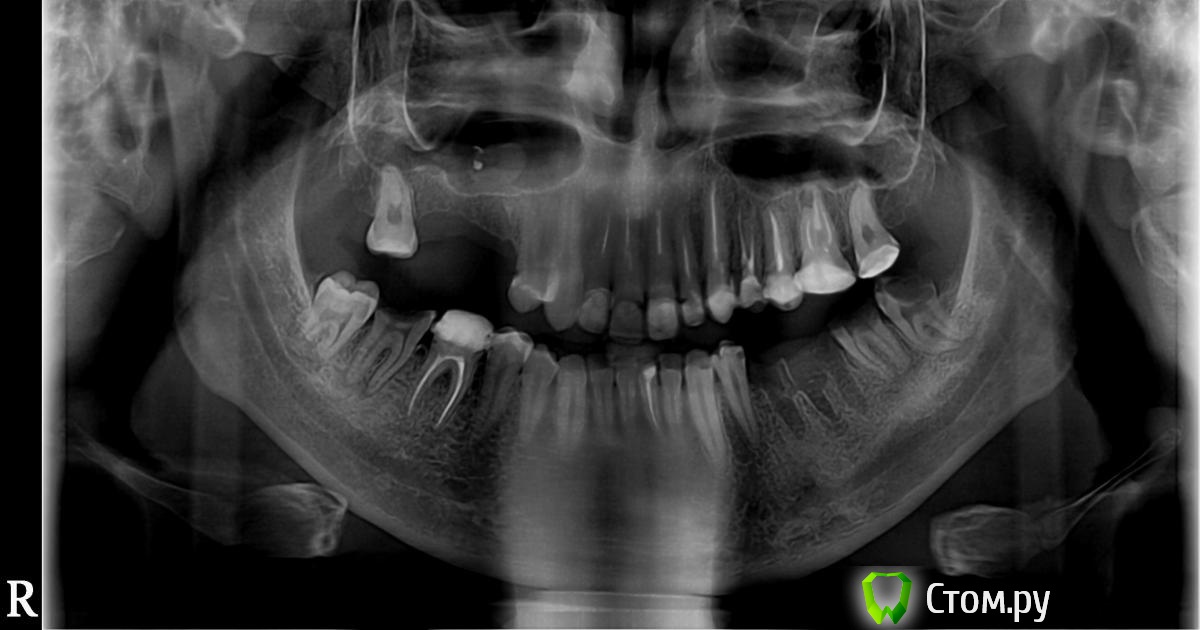

Bier Опубликовано 10 апреля, 2014 Поделиться Опубликовано 10 апреля, 2014 Хочу провести имплантацию отсутствующих жевательных зубов.Обязательно ли удалять для этого инородный материал из пазухи?Какие зубы лучше перелечить/удалить?Хочу услышать мнения людей с форума, чтобы сравнить с тем что мне скажет на консультации имплантолог.И еще может быть не в тему. На форуме читал что не стоит доверяться медицинским ВУЗам мол делают там плохо, по крайней мере читал так про Москву. Стоит ли проводить имплантацию в известном мед.вузе СПБ (какой я думаю все поняли)?Заранее спасибо за ответыВуз не советую.Материал из пазухи надо убрать (это как раз можно сделать в ВУЗе, ЛОРы там есть толковые).26, 37(?) 47(?) - лечить (?) - возможно удалять, надо смотреть во рту.38,48 - удалять. Ссылка на комментарий